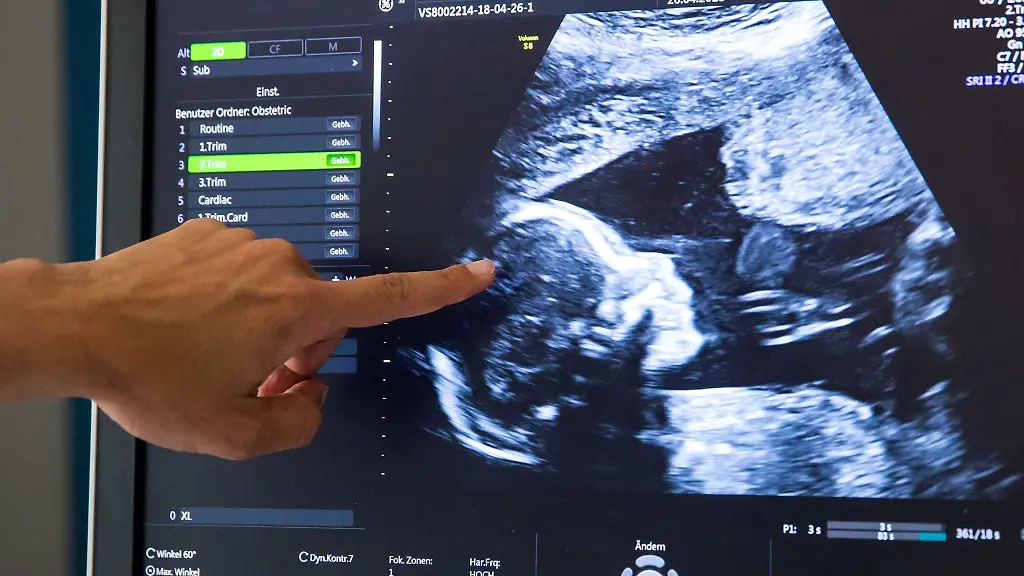

Haben Föten bereits ein sogenanntes Mikrobiom? Ein internationales Team widerspricht dem deutlich: Aufgrund einer multidisziplinären Analyse, die im Fachblatt "Nature" veröffentlicht wurde, stellte es fest, dass der Mutterleib gewöhnlich steril ist. Unser Mikrobiom, also die Gesamtheit aller Mikroorganismen, die sich in und auf der Haut, den Schleimhäuten und den Organen befindet, spielt eine zentrale Rolle für unsere Gesundheit und unser Immunsystem. Über jenes Immunsystem verfügen bereits Neugeborene – seine Entstehung stellt die Wissenschaft allerdings noch vor Fragen und dabei insbesondere vor die, wann ein Fötus zum ersten Mal mit Bakterien, Viren und anderen Mikroben in Kontakt kommt.

Lange Zeit galt, dass das ungeborene Kind, sowie die Gebärmutter, in der es heranwächst, einschließlich der Plazenta (Mutterkuchen) und des Fruchtwassers bei einer gesunden Schwangerschaft steril sind. Seit 2010 berichtet jedoch mehrere Forschungsteams, Bakterien in Proben der Plazenta und des Fruchtwassers gefunden zu haben. Sie schlossen daraus auf das Vorhandensein eines fötalen Mikrobioms, was bedeuten würde, dass die gängige Vorstellung über die Entwicklung des Immunsystems beim Ungeborenen völlig neu bewertet werden müsste.